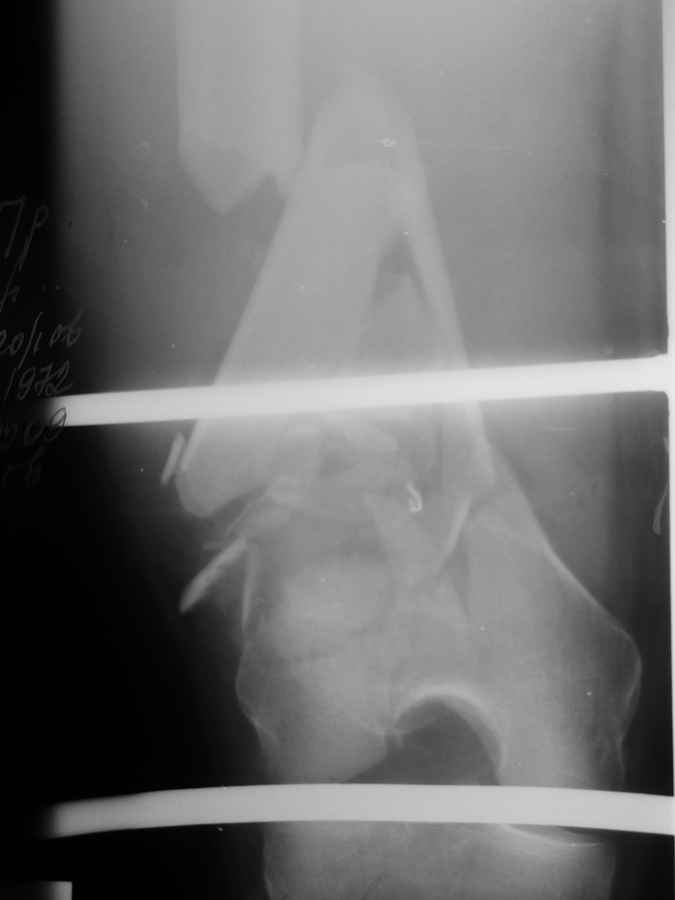

Уважаемые коллеги! подскажите тактику лечения(перелом нижней трети бедра)!

Операция, но какая? кто имеет опыт лечения таких переломов, если есть возможность предоставить подобные случаи! Мы планируем полноценную артротомию, собрать мыщелки на винтах и заштифтовать, у каких фирм подходящие фиксаторы и какие. Пациент - доктор хотелось бы помочь по максимуму. Спасибо за любую информацию.